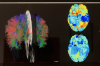

AIが「ジャンクDNA」と呼ばれる領域から自閉症に関連する遺伝子を発見することに成功 |